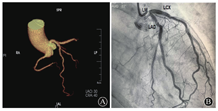

患者女性,53岁,因"反复胸闷,活动后气促"就诊,查体:呼吸20次/min,脉搏104次/min,血压121/89 mmHg。心界向左扩大,心率110次/min,心房颤动节律,心尖可闻及3/6级收缩期吹风样杂音。既往有高血压病史,规律服用贝那普利10 mg/d,血压控制不佳。心电图提示:持续性心房颤动(图1)。经胸壁超声心动图(TEE)提示:(1)二尖瓣重度关闭不全致左房、左室增大;(2)左室憩室形成(二尖瓣后瓣环)(图2)。心脏CT提示:(1)左心增大,二尖瓣后叶根部-左心室后下壁膨出瘤(真性)可能;(2)前降支(LAD)近端轻度狭窄约20%,第二对角支(D2)起始处中度狭窄约60%(图3)。为排外冠状动脉病变行冠状动脉造影检查,结果提示:右冠优势(+),左主干(LM)、LAD、回旋支(LCX)、右冠状动脉(RCA)未见明显狭窄(图4)。

可见左心增大,二尖瓣后瓣根部-左室后下壁局限性变薄并向外呈囊袋状凸出(箭头所示),大小约2.1 cm×2.0 cm,瘤颈约0.7 cm,边缘见钙化

A:左前降支近端轻度狭窄约20%, D2起始处中度狭窄约60%; B:冠状动脉未见狭窄